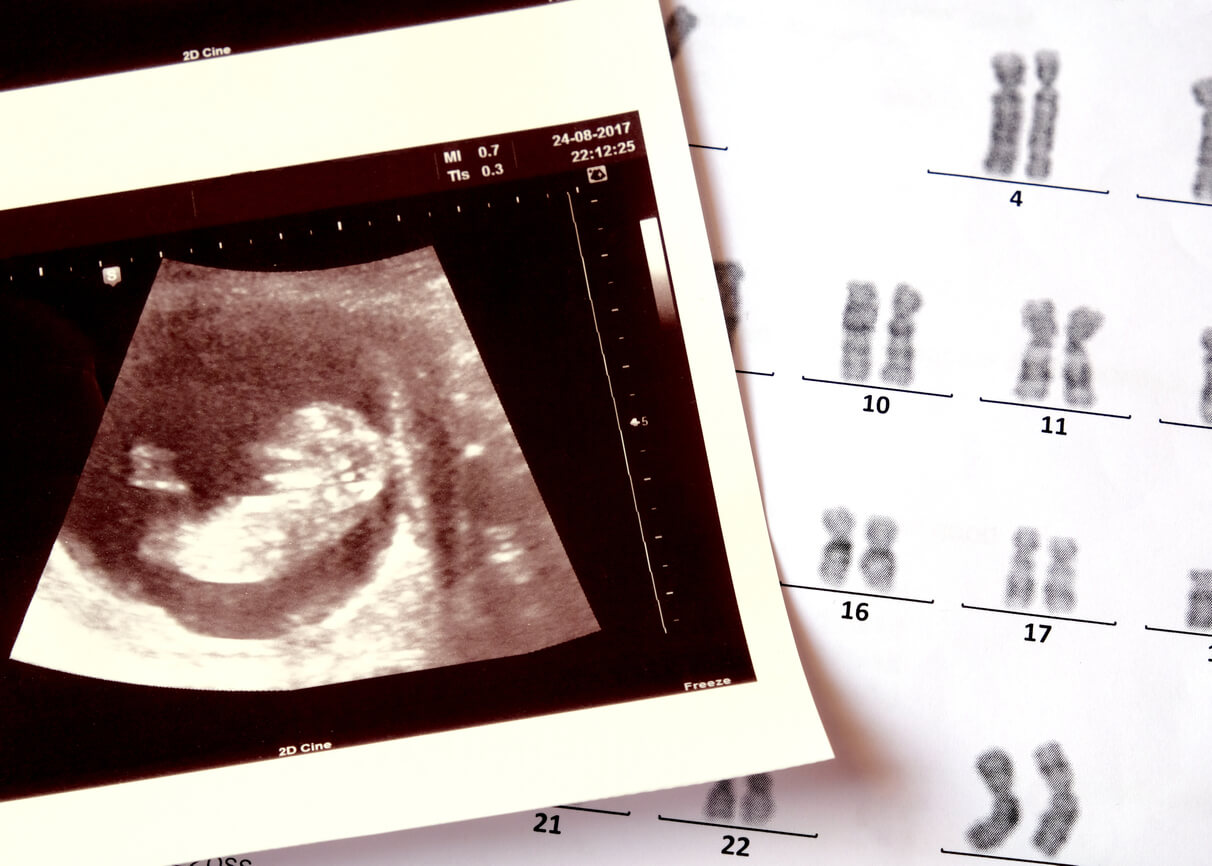

Los expertos del Centro para el Control y Diagnóstico de Enfermedades (CDC) aseguran que todavía no se conoce con exactitud las causas de la anencefalia, pero se sabe que ocurre como resultado de la interacción entre factores genéticos y ambientales.

Las alteraciones cromosómicas (unas estructuras que albergan todos los genes de las células) y algunas mutaciones puntuales podrían contribuir a su aparición. También se ha estudiado que la exposición a algunas toxinas ambientales podría ser determinante, aunque por el momento los resultados de las investigaciones no son concluyentes.